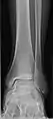

• Ankle - AP/Mortice and Lateral